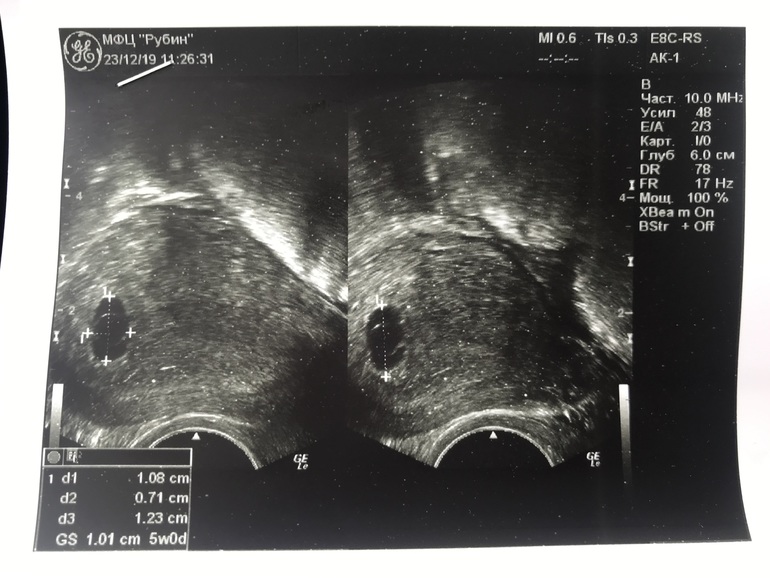

Нет эмбриона на 6 неделе

УЗИ, КТГ, доплерДевочки у кого так было, появился ли эмбрион? Врач сказала что возможна неравивающ.бер

К сожалению, динамика ХГЧ просто никакая, увеличен желточный мешок (большой риск ха), свд плодного яйца не соответствует сроку. Все вместе позволяет сделать неутешительные выводы(( на таком сроке эмбрион виден четко вместе с сб. А предположить позднюю овуляцию не даёт плохая динамика ХГЧ.